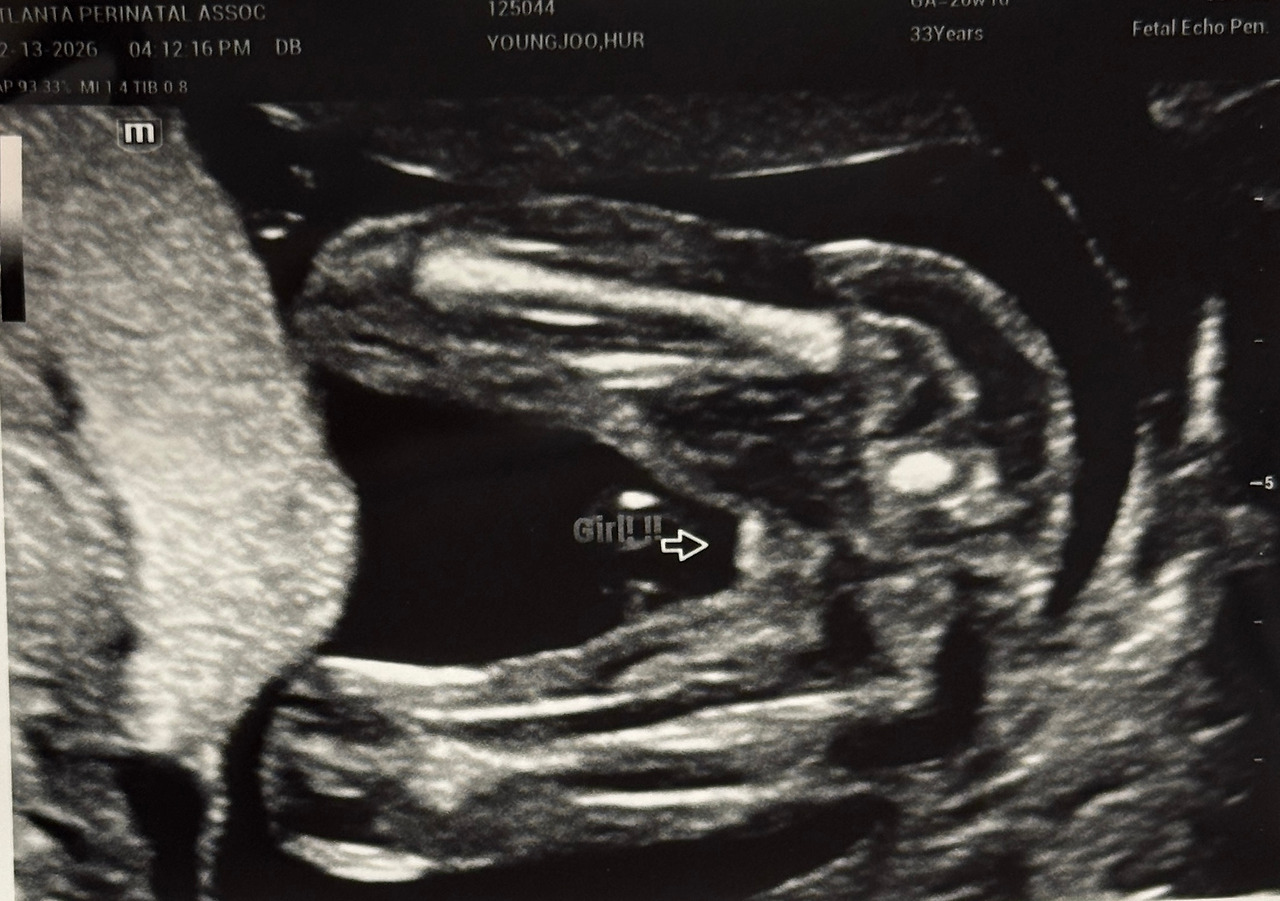

20주 정밀 초음파에서 본 나무. 꼬물꼬물 움직이는게 신기했다.